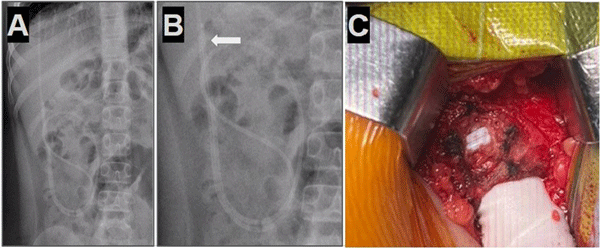

Caso 3. Paciente femenina de 7 años con antecedentes de síndrome de Moebius, hidrocefalia congénita y colocación de DVP al nacer que presentó vómitos e irritabilidad. Tomografía de cerebro simple evidenció dilatación ventricular en comparación con imágenes previas. Radiografía de sistema mostró catéter distal fuera de la cavidad peritoneal (Figura 3).

Figura 3. Caso 3: A) Se observa Rx de tórax y abdomen (frente) con catéter distal a nivel abdominal con migración retrógrada. B) Magnificación de Rx de abdomen que evidenció catéter en doble caño con signo radiológico del “caño de escopeta” o “signo del anzuelo” (flecha blanca) C) Imagen intraoperatoria que muestra la regresión del catéter en disposición paralela con la imagen típica de “doble caño” o “caño de escopeta”.